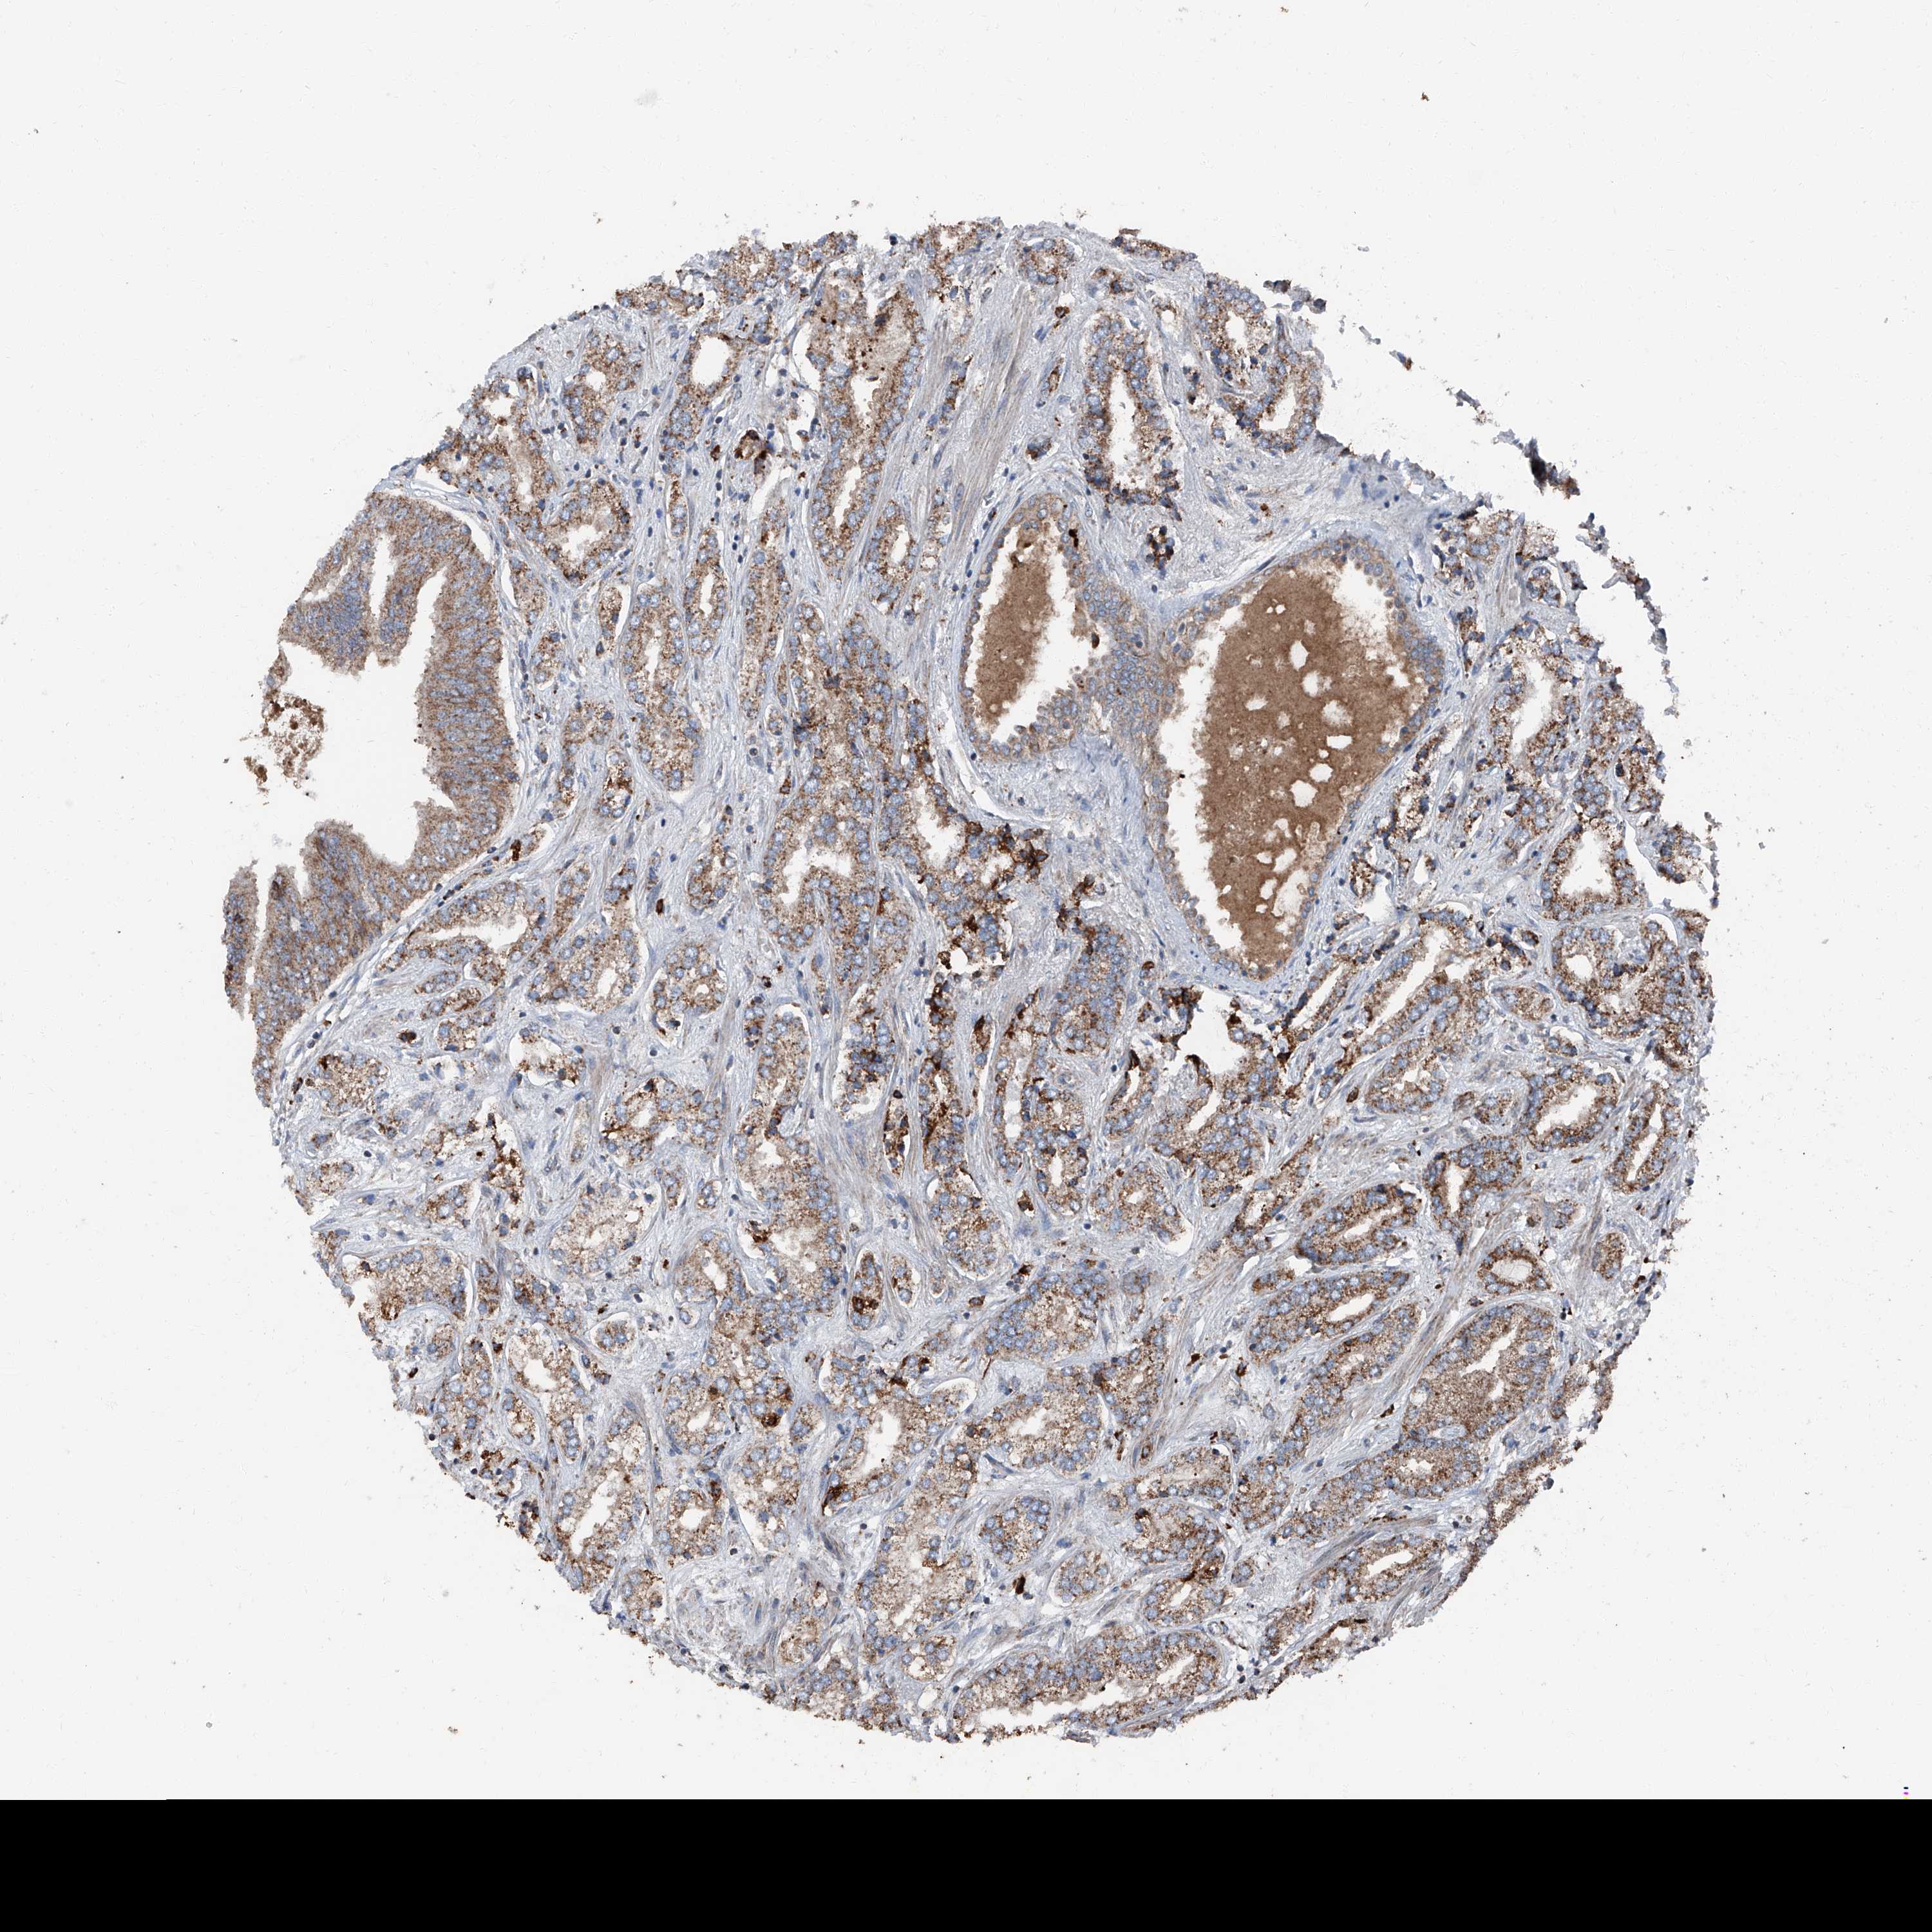

PROSTATE CANCER - Protein expressioni

A mouse-over function shows sample information and annotation data. Click on an image to view it in a full screen mode. Samples can be filtered based on level of antibody staining by selecting one or several of the following categories: high, medium, low and not detected. The assay and annotation is described here.

Antibody stainingi

Antibody staining in the annotated cell types in the current human tissue is reported as not detected, low, medium, or high, based on conventional immunohistochemistry profiling in selected tissues. This score is based on the combination of the staining intensity and fraction of stained cells.

Each image is clickable and will lead to virtual microscopy that enables deeper exploration of all samples and also displays staining intensity scores, fraction scores and subcellular localization as well as patient and tissue information for each sample.

Antibody HPA028516

Antibody HPA073571

Staining

High

Medium

Low

Not detected

Intensity

Strong

Moderate

Weak

Negative

Quantity

>75%

75%-25%

<25%

None

Location

Nuclear

Cytoplasmic/membranous

Cytoplasmic/membranous,nuclear

Adenocarcinoma, High grade

Adenocarcinoma, Low grade

Adenocarcinoma, Medium grade

Adenocarcinoma, NOS